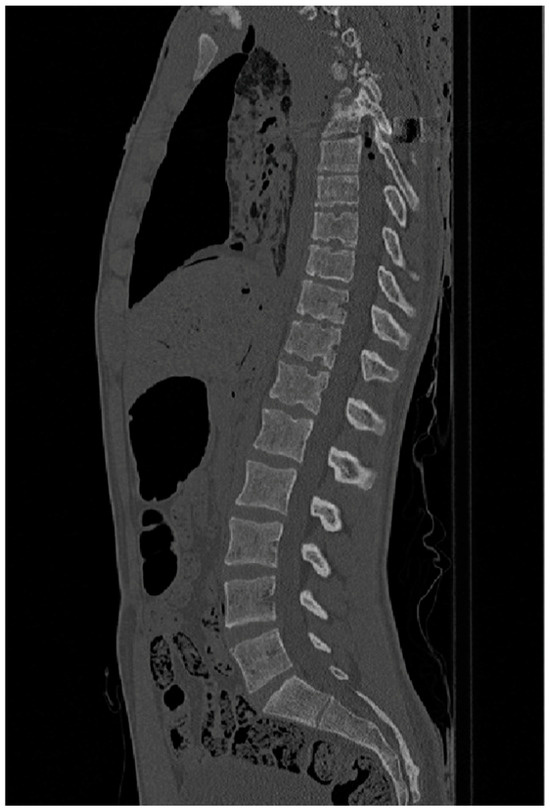

The CT scans were provided by the New Mexico Decedent Image Database; therefore, no CT imaging equipment was needed in this research to gather the images. The machine used by the researchers from the NMDID to perform the scans was a Phillips Brilliance Big Bore with a Radiation Therapy flat carbon fibre top, producing images like the ones shown in Figure 2 and Figure 3.

Figure 3.

CT slice in the transverse plane from ID 105469 used to measure vertebral densities. Reprinted with permission from [16].

To identify the presence of any Schmorl’s nodes, Thermo Fisher Scientific’s Avizo Lite software was used to set the CT scans in different planes to allow for the visualization of the layers. Three-dimensional models were then also constructed from the scans to provide a detailed image. Along with the segmentation images, this was used to identify any Schmorl’s nodes in the individuals (Figure 2 and Figure 3).

To take density values, ImageJ v.1.53 was then used, which allows the layers in certain planes to be viewed. ImageJ is a free software that allows image files to be uploaded and for regions of interest (ROIs) to be created either automatically or manually. The CT scans were uploaded as DICOM files; the transverse plane images were loaded into the software, which allowed the segmentation layers to be scrolled through until vertebrae L3, L2, L1, T12, and T11 were located (Figure 3). These vertebrae were selected due to the high frequency of this region being affected by Schmorl’s nodes and scoliosis [17]. The density of the vertebral bodies was calculated in each case in Hounsfield units and was already calibrated for, as the images were in the DICOM format. Using the oval selection tool within ImageJ, the ROI was created, and measurements of density were taken in the middle of each vertebral body in the centre-most point, from the inferior side. All measurements were within a centimetre of each other as the size did vary with age.